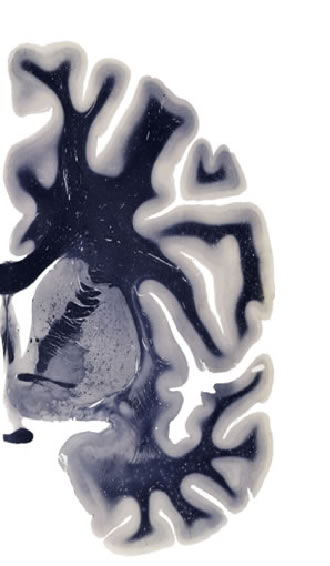

Hi-Resolution Sections · Cells (Nissl Staining) · Virtual Microscopy

Frontal sections (Nissl) from the Atlas Brain:

Slice ID:

r3-1418

Plate NR:

ca 21

Position:

-0,44 mm